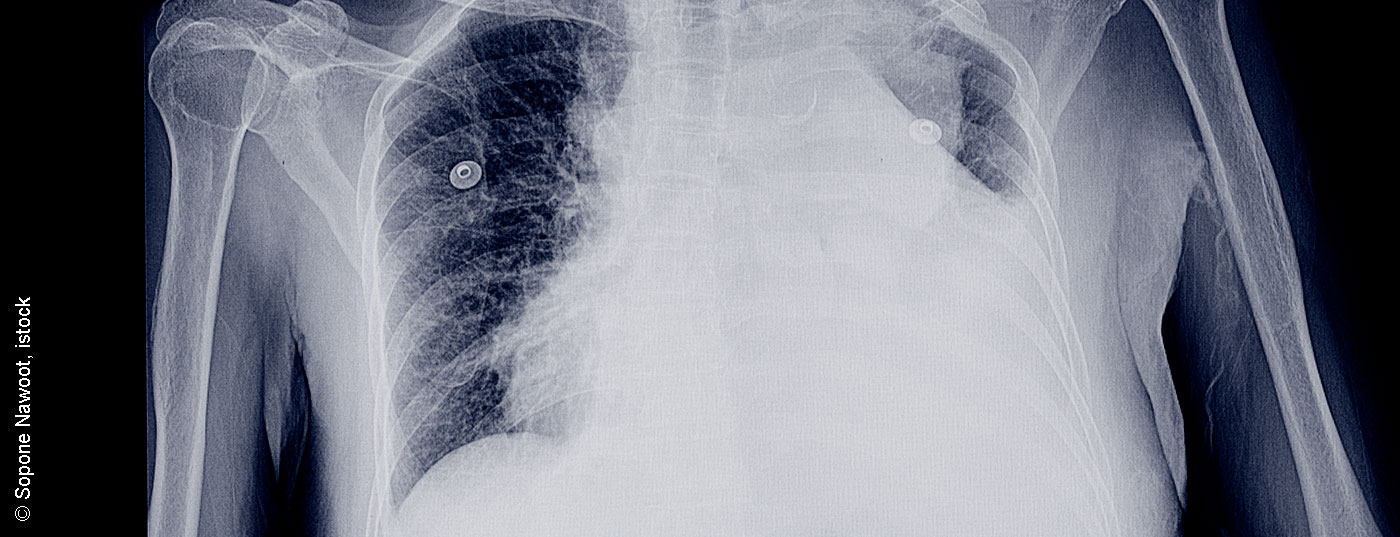

pleuraerguss_istock-952689296

• Pleuraerkrankungen in der Thoraxsonografie

Ätiologische Differenzierung mittels Sono

Die Pleura bedeckt als seröse Schicht die Thoraxorgane und die innere Skelettseite zur Thoraxhöhle. Die geringe Normalmenge an Pleuraflüssigkeit, die für ein reizfreies Pleuragleiten verantwortlich ist, wird hauptsächlich in der parietalen Pleura sowohl produziert als auch über Lymphwege resorbiert.